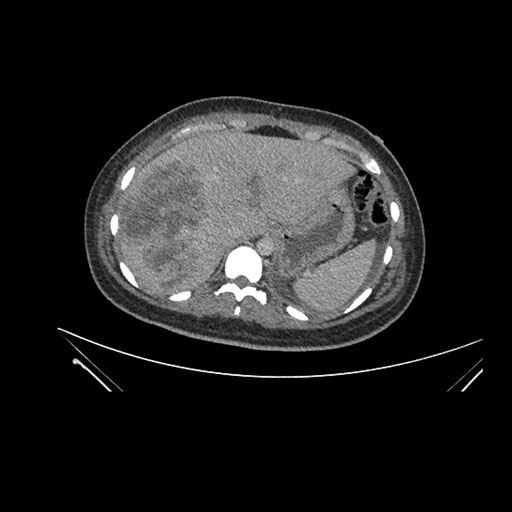

Imaging Analysis

Look through the patient's CT scan to identify any areas of concern for the necessary procedure.

Coronal Venous

Based on initial findings, which issue(s) would you be most concerned about?